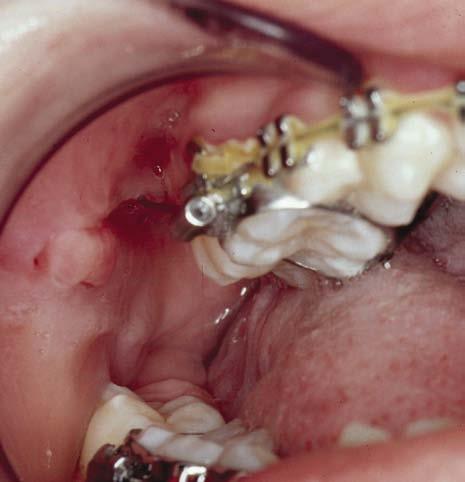

Gingivitis

Gingival irritation is inevitable with the use of fixed appliances, especially the placement of bands and this is exacerbated by poor oral hygiene, which can result in gingival hyperplasia. Gingival health improves significantly following the removal of appliances, with a reduction in probing depths mainly due to shrinkage of hyperplastic tissues (Fig. 1.18). Certain medications such as antiepileptic drugs and immunosuppressants in combination with poor oral hygiene can result in extensive gingival hyperplasia that can require gingival surgery following appliance removal.